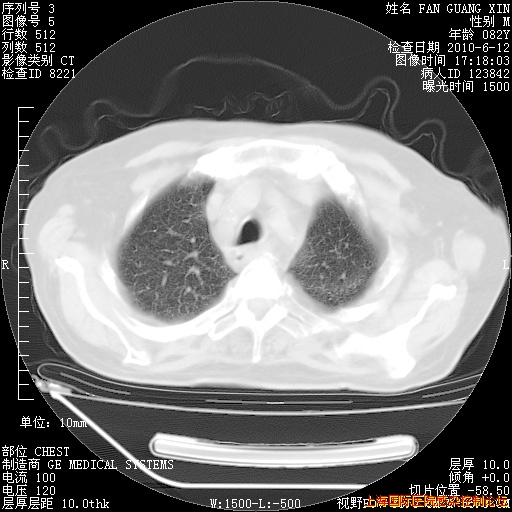

6月10日改甲强龙80mg qd ,在南京年会期间体温不稳,18日有一次寒战后体温达39度。19日开始用甲强龙60mg bid ,加量后第二天就不发热。本打算在两周后即7月3日减量,但是7月2日洗澡受凉、发热、咳嗽、鼻音,口服复方大青叶片,甲强龙120mg用到9日(整整20天)。

自昨天起甲强龙改为80mg qd。

在抗结核治疗2周后一般情况逐渐好转。

今天复查CT

整整相隔30天的肺部CT好像有所好转啊。甲强龙减量第3天,需要观察体温。

海管,自昨日你和我通完话后,不知您岳父消化道症状有无缓解?体温怎样?阅读7.12日胸部ct,个人认为目前激素治疗是有效的,甲强龙减量是适宜的。因在抗痨治疗,需密切观察肝功、肾功能和血常规。不过,老年、长期住院和大量使用激素,很担心菌群失调发生